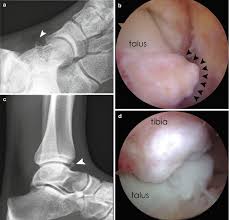

Osteoarthritis Of The Ankle Methods For Joint Preservation Joint Surgeon Com

Osteoarthritis Of The Ankle Methods For Joint Preservation Joint Surgeon Com from gelenk-klinik.de

Traumatic dislocation of tibialis posterior presenting late as a bony spur. The relationship between spur formation, the medial tubercle of the calcaneus and intrinsic heel musculature results in a constant pulling effect on the plantar fascia resulting in an inflammatory. It may also involve injury to a ligament. What are treatment options for a bone spur? The medial malleolus is the largest of the three bone segments that form your ankle. Small well corticated bony fragments lies at the anterior aspect of the medial malleolus. The other two are the lateral and the posterior malleolus. The medial malleolus is the medial projection of bone from the distal tibia. Bone spurs are bony projections that develop along bone edges. The tibia (shin bone) is the medial bone of the leg and is larger than the fibula, with which it is paired (figure 3). The fibula is commonly shortened and externally rotated in a malunion, although only one of these may be present, determining the type of osteotomy and bone. Ankle joint dislocation is often associated with fracture of medial malleolus bone. Nkle sprain, medial malleolus, pseudoarthrosis radiographs of the medial malleolus showed jagged.